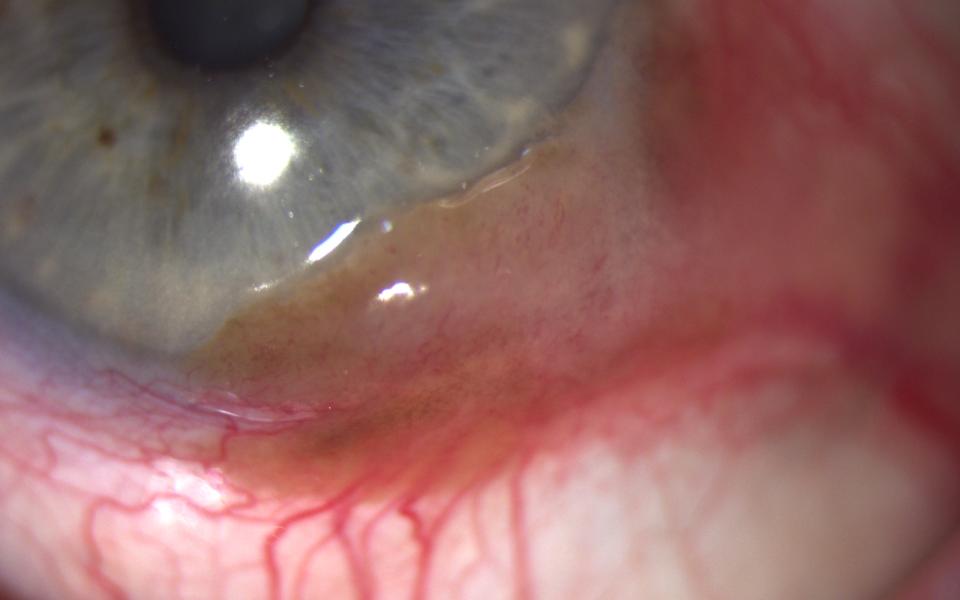

78 Male presenting with blurring of vision for 4 months. Slit lamp examination demonstrated corneal OSSN, with characteristic fimbriated margin. He was commenced on topical interferon alpha-2b 1